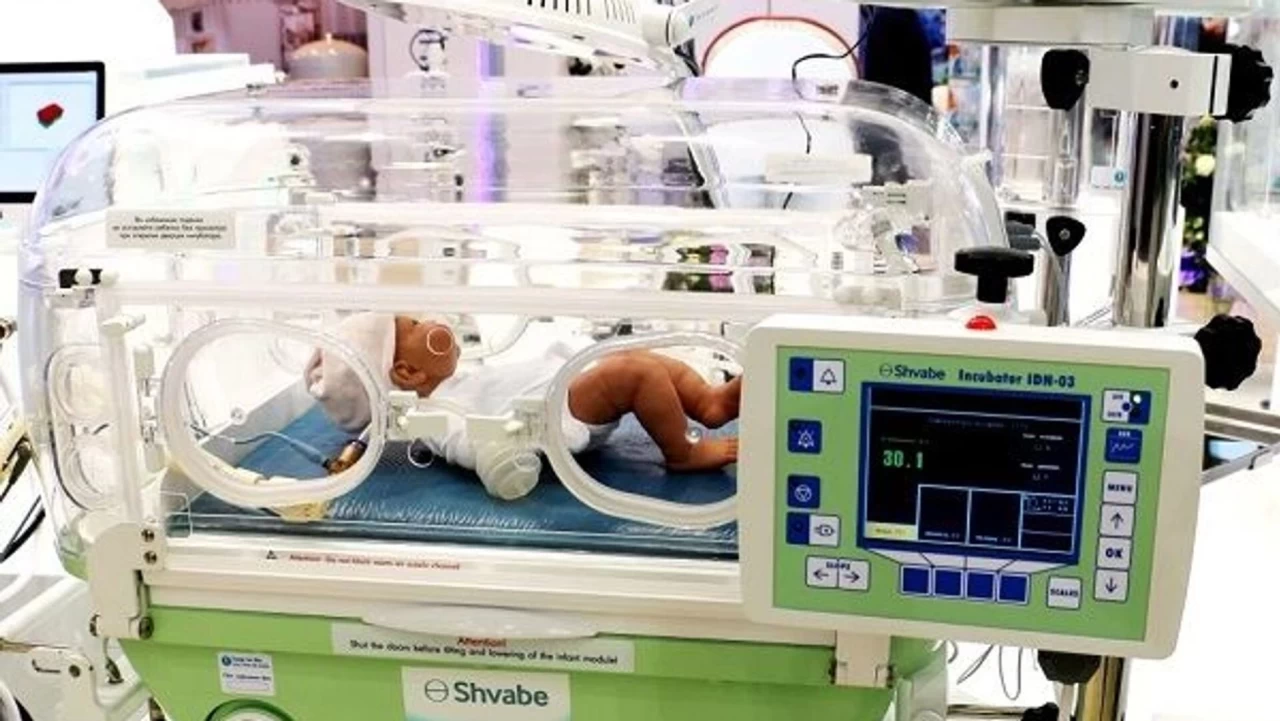

Müşteki M.H.K, doğumun ardından kendisi, eşi ve çocuğunun 3 gün hastanede kaldığını aktararak, "Çocuğum yoğun bakım ünitesinde kaldığı süre zarfınca iki kez Dr. Songül Hanım tarafından bilgilendirildim. Bana bebeğimin iyi olduğu bilgisi Songül Hoca tarafından verildi. İkinci gün Songül Hanım, eşimin durumunun iyi olduğunu fakat çocuğumun durumunun iyi olmadığı bilgisini verdi. Üçüncü gün olan 16 Kasım 2023 günü, gece 04.00 sıralarında da çocuğumuz vefat etti. Vefat haberini öğrendikten sonra hastaneden çıkış işlemlerini yaparak ayrıldık" ifadelerini kullandı.

Doktorların doğumdan sonra bebeğin durumunun iyi olduğunu, herhangi bir sıkıntısının olmadığını söylediklerini aktaran E.K, "27 Kasım'da bebeğimin doğumuyla ilgilenen N.T. isimli doktor bize bebeğin durumunun kötüleştiğini ve acil olarak sevk edilmesi gerektiğini söyledi. Saat 03.00-04.00 sıralarında bebeğim Özel Bağcılar Medilife Hastanesine sevk edildi. Bu sırada bebeğimin rahatsızlığı ile alakalı herhangi bir tanı konulmamıştı" diye konuştu.

Özel Bağcılar Medilife Hastanesinde bebeğiyle ilgilenen şüpheli doktor Dursun Eryılmaz'ın, kendilerine bebekte kalp yetmezliği olduğu ve metabolik hastalık bulunduğu bilgisini verdiğini belirten E.K. şunları kaydetti:

"Eğer yaşarsa yüzde 80 ihtimalle bebeğin engelli olacağını ya da öleceğini söylediler. Dr. Dursun Eryılmaz, bebeğime anne sütü vermek için beni eşimin yanına gönderdi. Eşimin yanına giderken hastaneden tekrardan arandım ve bebeğimin durumunun kötüleştiğini, acil olarak hastaneye geri dönmem gerektiğini söylediler. Ardından hastaneye gittim ve bebeğim hala yaşıyordu. Bana bebeğimin durumunun kötü olduğunu söylediler. Dışarıdan özel bir doktorun gelerek bebeğimi muayene edeceğini, bunun karşılığında da 3 bin TL civarı ödeme yapmam gerektiğini söylediler. Bebeğim ertesi gün vefat etti."

Müşteki baba H.H. de 26 Kasım 2023'te eşi G.E.H'nin doğum sürecinin başlaması üzerine gittikleri hastanede, yenidoğan yoğun bakım ünitesinde yer olmadığı gerekçesiyle Özel Bağcılar Medilife Hastanesi'ne sevk edildiklerini aktardı.

Aynı gün doğum yapan eşinin ve bebeğin durumunun iyi olduğu ancak bebeğin yenidoğan yoğun bakım ünitesinde kuvöze alınıp durumunun takip edileceği konusunda bilgilendirildiğini dile getiren H.H, "Bebek ile ilgili süreci yenidoğan yoğun bakım biriminin takip edeceğini söylediler. 29 Kasım günü sabah saatlerinde ismini Dursun (Eryılmaz) olarak bildiğim doktor ile görüştüm. Bebeğimin kalbinin gece 1-2 defa durduğunu, kalp masajı yapıp geri döndürdüklerini söyledi" dedi.

Müşteki Y.K, Yalova'da 2023 yılı ağustos ayında eşi S.K'nin, erken doğum yapacağı gerekçesiyle bebek yoğun bakımı olan İstanbul'daki Özel Bağcılar Medilife Hastanesi'ne sevk edildiğini kaydetti.

Y.K, 15 Ağustos'ta dünyaya gelen bebeğinin bağırsaklarının anne karnında çürüdüğü söylenerek ameliyat edildiğini, yaklaşık 2 ay yoğun bakımda kaldıktan sonra 19 Ekim 2023'te vefat ettiğini belirtti.

Yabancı uyruklu müşteki B.N.O. tercüman aracılığıyla alınan ifadesinde, 5 aylık kızını öksürük ve soğuk algınlığı şikayetiyle 14 Ocak 2024'te Beylikdüzü Medilife Hastanesine götürdüğünü, yapılan testler sonucu bebeğinin hastaneye yatırılmasının uygun görüldüğünü söyledi.

Bebeğinin bir gün normal odada kaldığını, ertesi gün yoğun bakım ünitesine alındığını belirten B.N.O, üçüncü günün sonunda doktorun, "Burası bir aylık bebekler için. Sizin bebeğiniz burada kalırsa ölür. Ona yeni bir hastane bulun" dediğini dile getirdi.

B.N.O, yoğun bakımdan sorumlu doktorun ise kendilerini günlük ücreti 7 bin lira olan Beylikdüzü Birinci Hastanesine yönlendirdiğini ve bebeğin 2 hafta tedavi sonucunda sağlığına kavuşacağını söylediğini aktardı.

Bebeğinin 17 Ocak'ta ambulansla sevk edildiğini ve 5 günlük yatış ücreti olan 35 bin lirayı peşin ödediğini kaydeden B.N.O, yaşadıklarını şöyle anlattı:

"Bebeğimi yenidoğan yoğun bakım ünitesine aldılar. Orada kuvöze koyduklarını gördüm. Benden bazı medical malzemeler olduğunu düşündüğüm şeyler istediler. Biberon, şampuan, bebek bezi ve bazı ilaçlar aldım. Ertesi gün sabah 08.00'de aradılar ve bebeğimin durumunun kötü olduğunu, hastaneye gelmemiz gerektiğini söylediler. Hastaneye gittiğimde bebeğimin sabah 06.00 sıralarında öldüğünü, geri döndürmeye çalıştıklarını ama başarılı olmadıklarını söylediler. Bebeğimi görmek istediğimde, yenidoğan yoğun bakım ünitesinde kuvözde bebeğimin ölü halini gösterdiler."